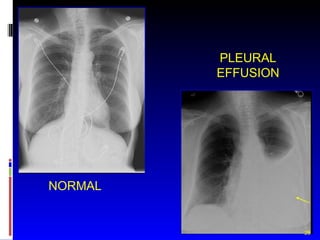

PLEURAL EFFUSION NORMAL

PLEURAL EFFUSION